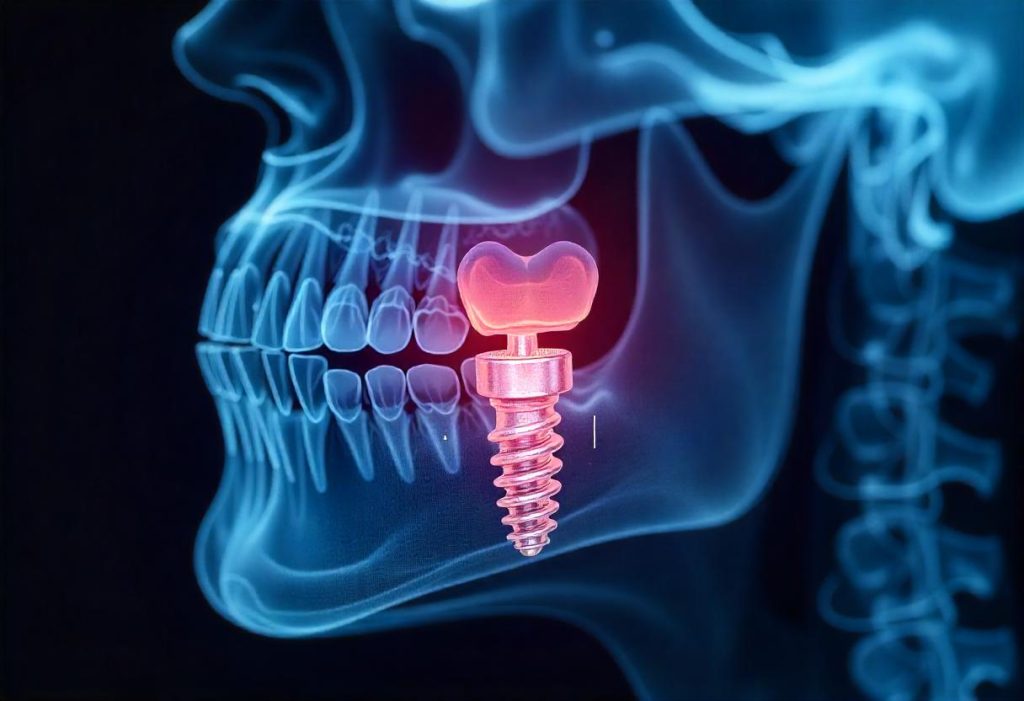

- Dental Implants: These are titanium posts surgically placed into the jawbone, acting as artificial tooth roots. Implants provide a strong and long-lasting solution for replacing missing teeth.

3. Dental Implants: A Permanent Solution for Missing Teeth

Dental implants are a popular choice for replacing missing teeth due to their numerous benefits.

- Benefits of implants:

- Improved appearance: Implants look and feel like natural teeth.

- Enhanced speech: They allow for clear speech.

- Increased comfort: Implants are securely anchored, eliminating the discomfort of loose dentures.

- Improved oral health: They help preserve jawbone health and prevent bone loss.